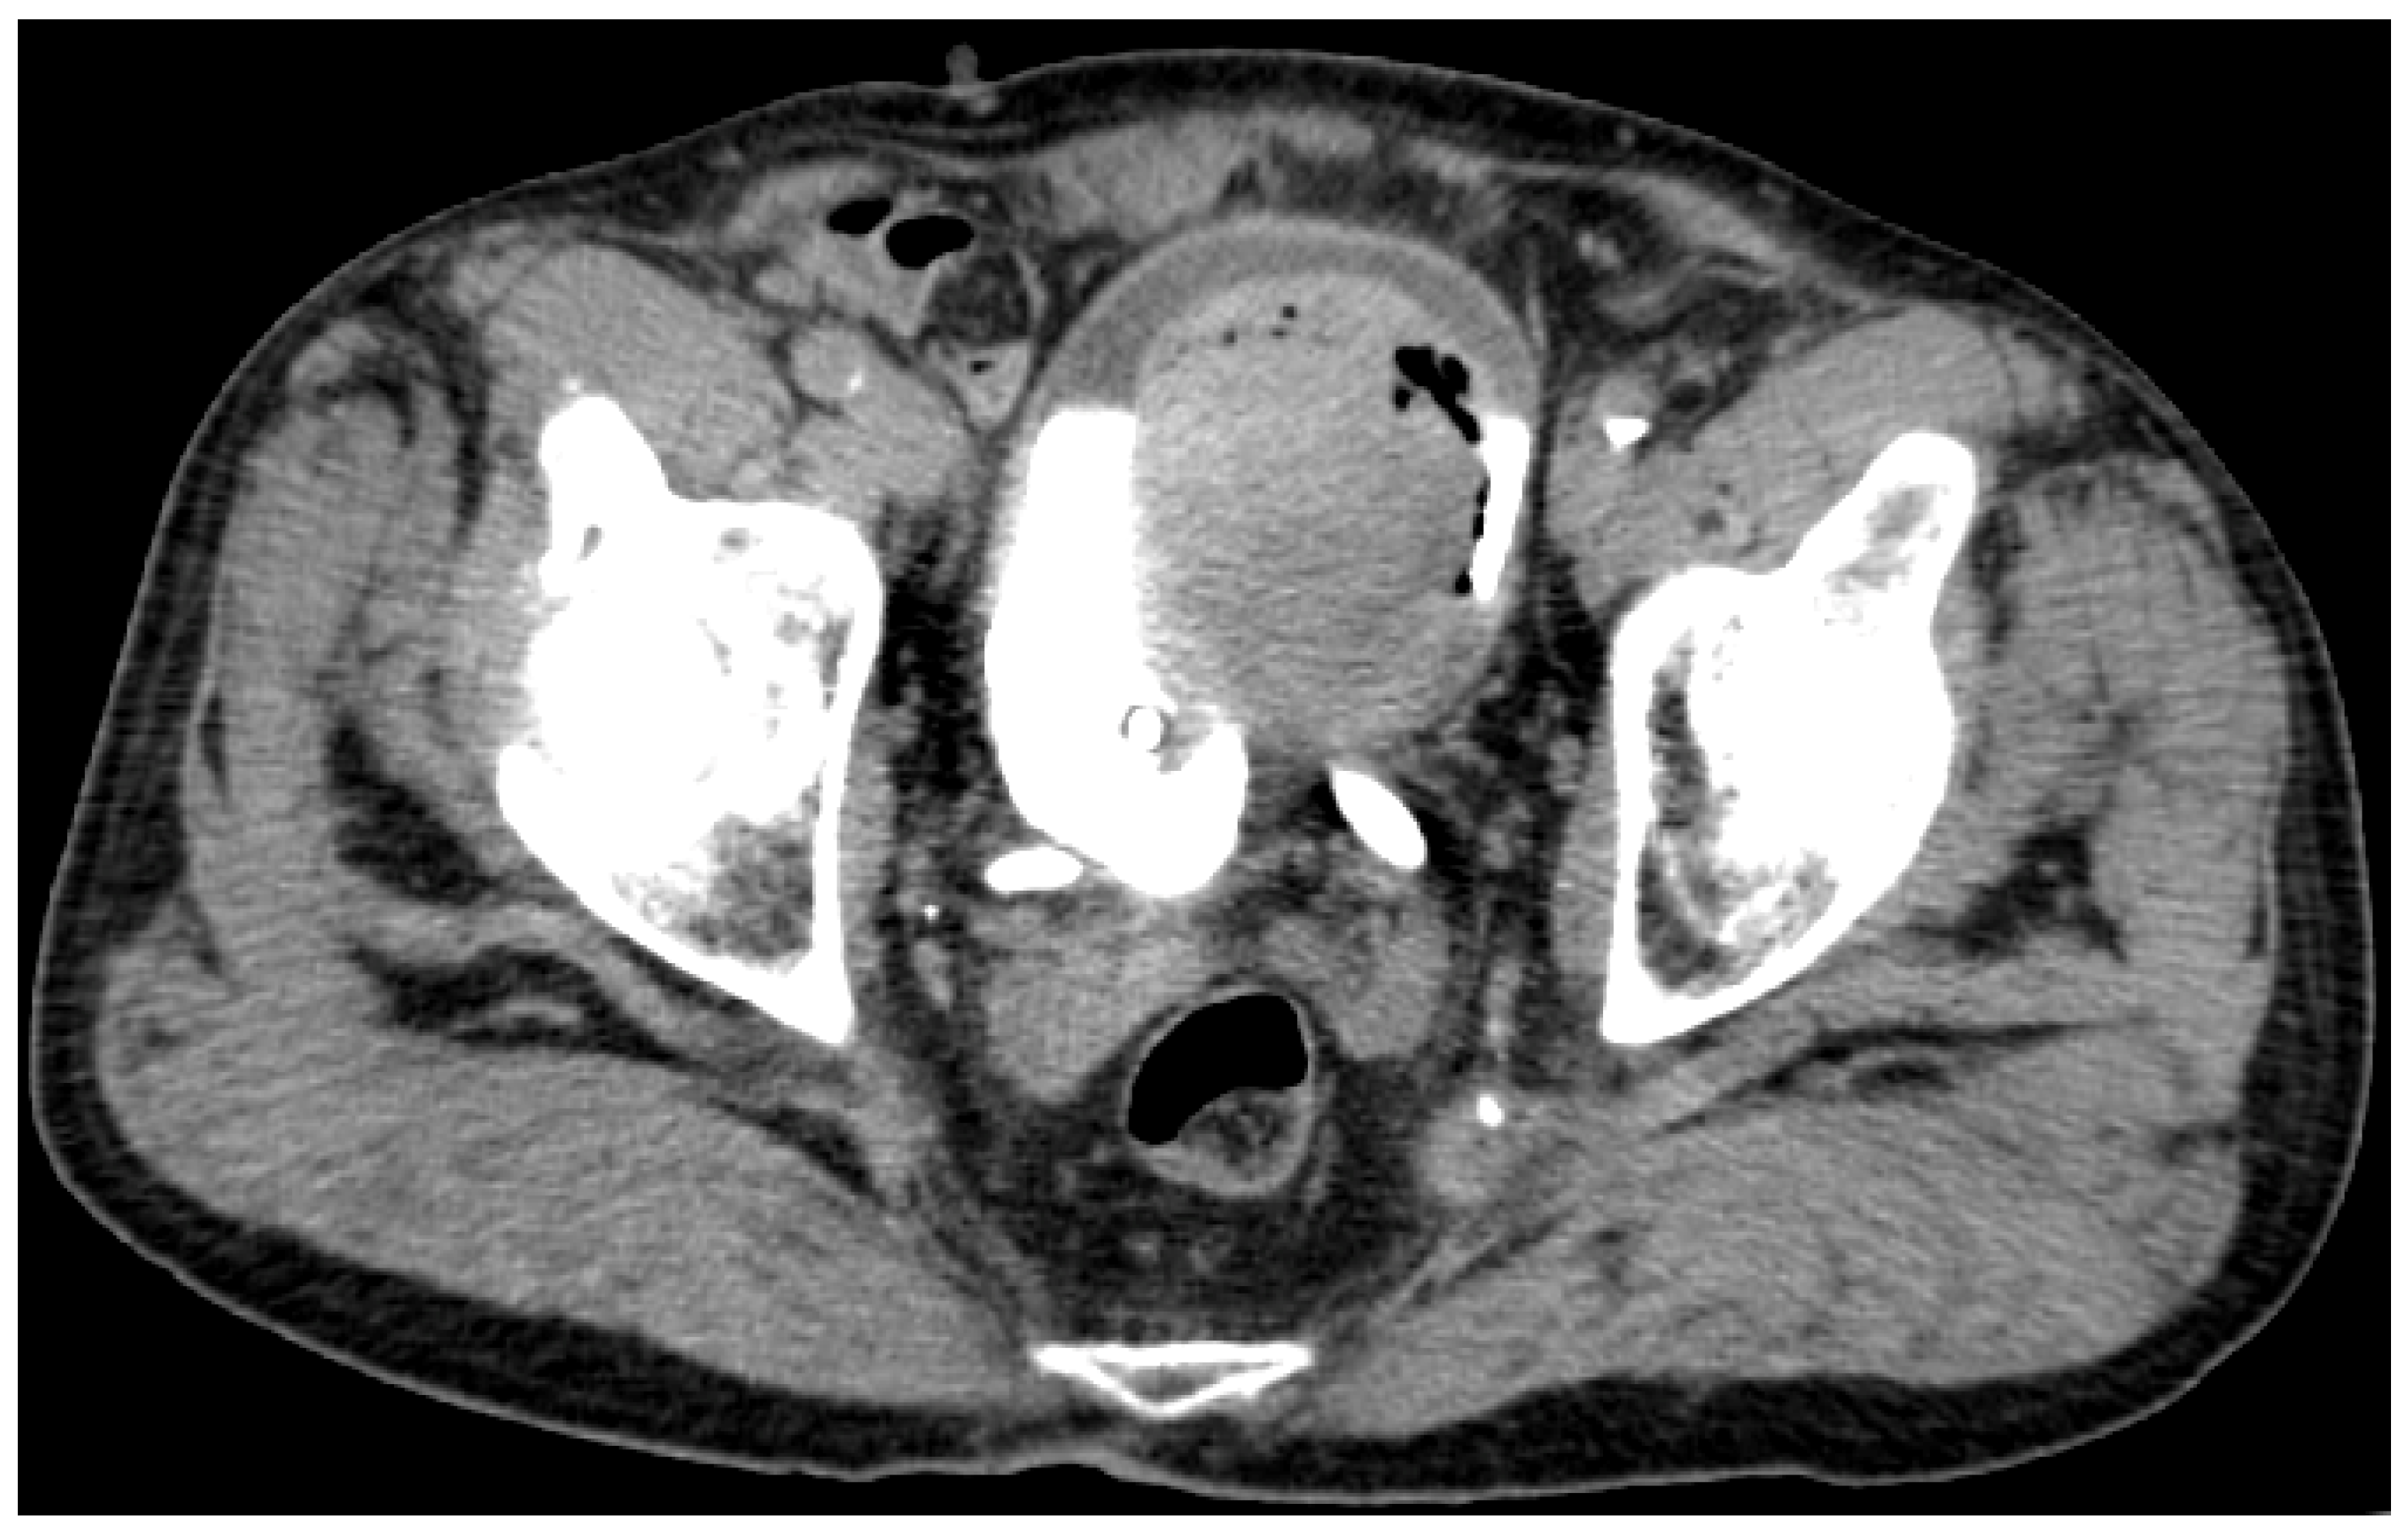

| 9 July 2020 | TURBT | - pT1G2 high grade (biopsy), i.e., large residual tumor. | Nivolumab |

| 30 September 2020 | Cistoscopy | - complete spontaneous tumor necrosis. | Nivolumab |